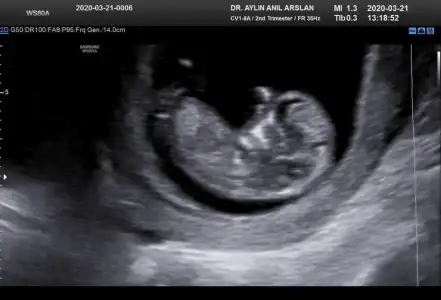

11+3 ama cok net değil gibi sanki yinede Bi tahmin isterim daha 5 hafta sonra öğrencez mecbur 😪

• IMG-20200321-WA0010.webp

IMG-20200321-WA0010.webp

25,9 KB · Görüntüleme: 44

• IMG-20200321-WA0011.webp

IMG-20200321-WA0011.webp

25,8 KB · Görüntüleme: 41

• IMG-20200321-WA0012.webp

IMG-20200321-WA0012.webp

25,8 KB · Görüntüleme: 40